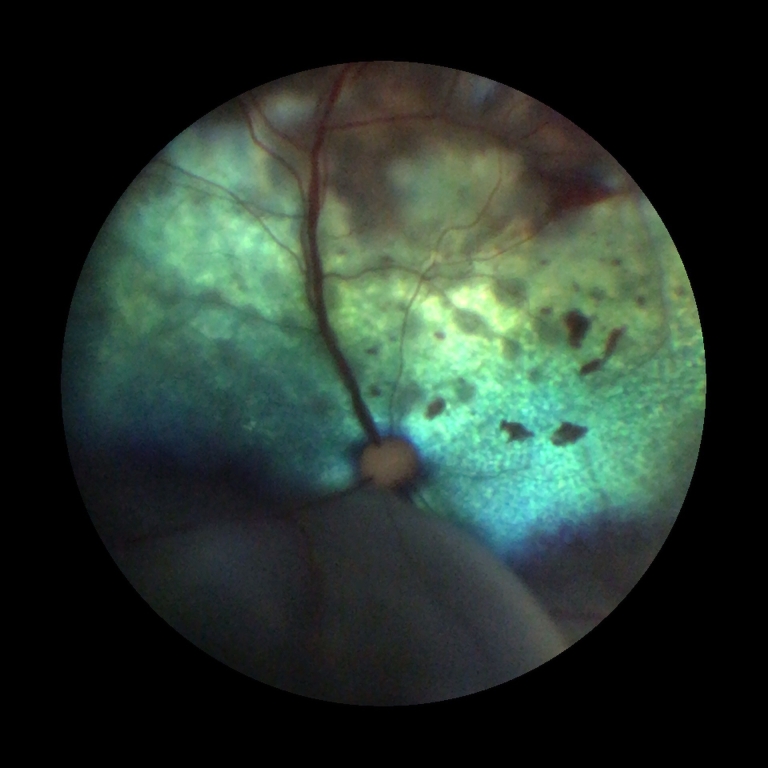

One of the UK’s leading small animal hospitals has added further to its impressive range of state-of-the-art equipment with the arrival of an ultra-modern fundus camera.